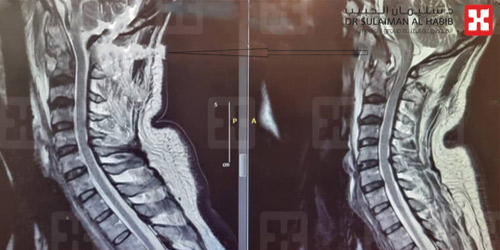

وقال د. ناجي مسعود استشاري جراحة المخ والأعصاب والعمود الفقري، رئيس الفريق الطبي المعالج، إن العملية التي أجريت للمريض تعد الأولى من نوعها في المملكة، ولم تُجْرَ منذ العام 1920م سوى «36» مرة على مستوى العالم، مضيفاً أن المريض سعودي الجنسية، وأدخل المستشفى عن طريق الطوارئ، وهو يعاني من شلل كامل للشق الأيسر من الجسم، وضعف في التنفس، وحالة دوار مستمرة، وأخضع لحزمة من الفحوصات الطبية الدقيقة، ومن أهمها الأشعة المقطعية CT- Scan والرنين المغنطيسي MRI، وبينت الصور والتحاليل وجود كتلة صديدية كبيرة الحجم جزء منه سائل والآخر صلب، وتسبب ضغطاً شديداً على أكثر من منطقة حساسة ما نتج عنه الأعراض الحادة التي عانى منها المريض.

وأضاف د. مسعود أن الفريق الطبي أخضع الحالة لدراسة عميقة، وخلص إلى خطة علاجية مكونة من مرحلتين، وبعد إكمال الترتيبات اللازمة أخضع المريض في المرحلة الأولى إلى عملية دقيقة ومعقدة، تم الدخول فيها عبر الفم، حيث تم رفع اللهاة وفتح الطريق إلى الجدار الخلفي للبلعوم، والوصول عبره إلى الفقرة الأولى، ومن ثم إلى الفقرة الثانية التي بها الصديد والالتهاب الشديد، وتمت إزالة الكتلة بالكامل، وتحريرعنق الدماغ والنخاع الشوكي من الضغط فعادا إلى وضعهما الطبيعي، وتكللت العملية التي استمرت لنحو «6» ساعات، ولله الحمد بالنجاح التام، ونقل المريض إلى العناية المركزة، حيث بقي فيها تحت التنفس الاصطناعي حتى موعد العملية الثانية، التي جرت بعد «5» أيام، وتم فيها تثبيت الفقرتين الأولى والثانية، ثم أعيد إلى العناية المركزة، وبدأت حالته الصحية في التحسن بنسق متسارع، حيث رفع عنه جهاز التنفس الاصطناعي بعد «72» ساعة من العملية الثانية، وبدأ يحرك أطراف شقه الأيسر الذي كان مصاباً بالشلل التام، وفي اليوم السادس نقل إلى غرفة تنويم اعتيادية وبدأ يمشي بمساعدة «المشاية» وبعد نحو أسبوعين خرج من المستشفى على قدميه وسط فرحة كبيرة من أهله، والآن عاد إلى عمله وممارسة حياته اليومية بصورة طبيعية.